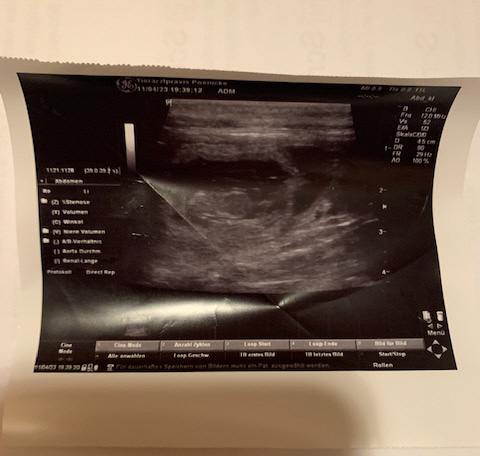

Heute am 04.12.2023 waren wir zum Ultraschall.

Ja, Volltreffer meinte der Tierarzt. Und so erwarten

wir Anfang Januar unseren B-Wurf.

Heute am 11.04.2023 war ich mit Lena zum Ultraschall und es wurden 5 Fruchtblasen festgestellt.

Der Wurf wird am 14.05.2023 erwartet!

28.Trächtigkeitstag.